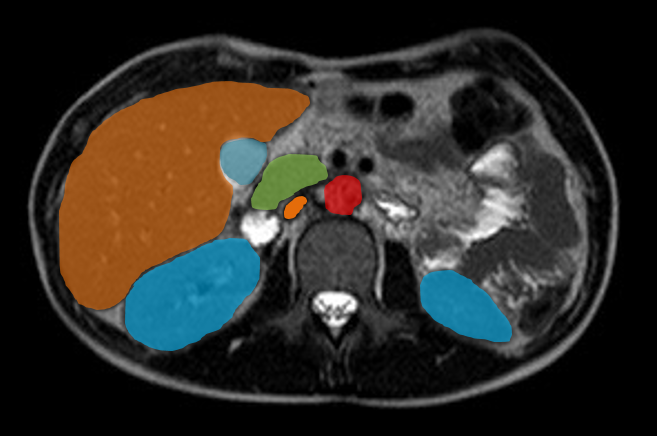

Bildergalerie (5 Bilder)

1 (Bild 1 von 5) Vorwärts »

« Zurück 5 (Bild 5 von 5)